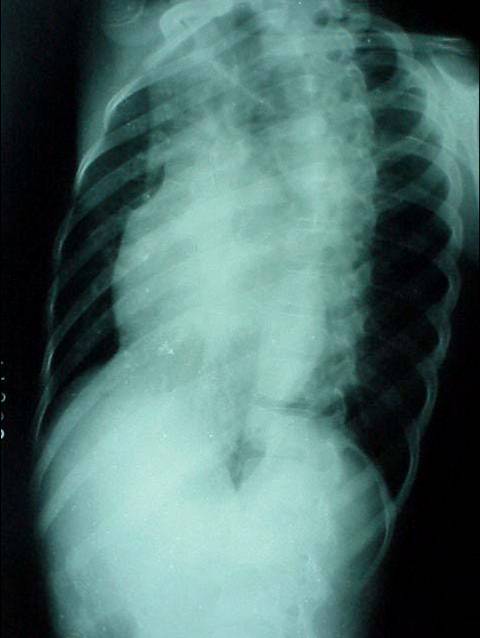

照片名称:大量胸腔积液